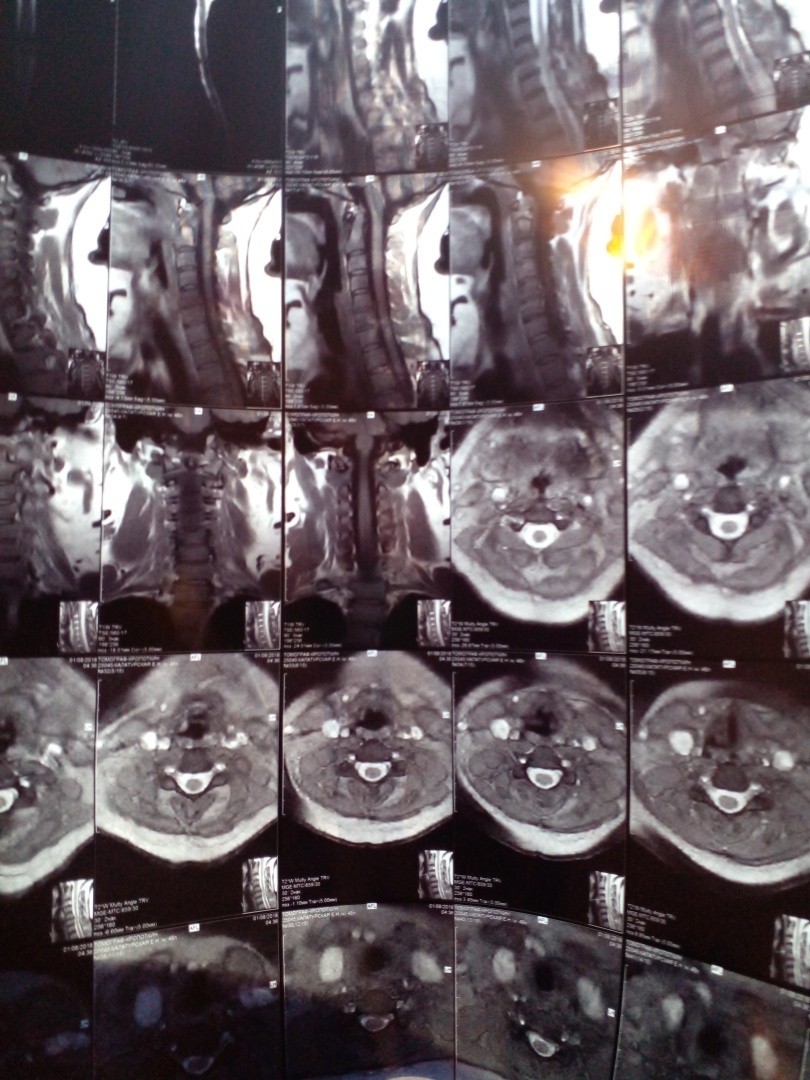

Здравствуйте, очень нужна помощь . буду откровенна нужна финансовая помощь. У моей мамы с 2018 года стоит диагностика русскими словами - разрушение позвоночника. От операции она отказывается , так как на нее нужны большие деньги, которой нашей семье на под силу. Я пробовала взять кредит , но мне не дают , так как нахожусь в декрете . С каждым годом ей становится хуже , она сейчас без обезболивающего даже с кровати подняться не может , боли очень сильные . операция стоит от 300 000 до 500 000 рублей , все зависит сейчас от степени разрушения . очень прошу помочь кто сколько сможет . ( 2202201647761309 сбербанк )